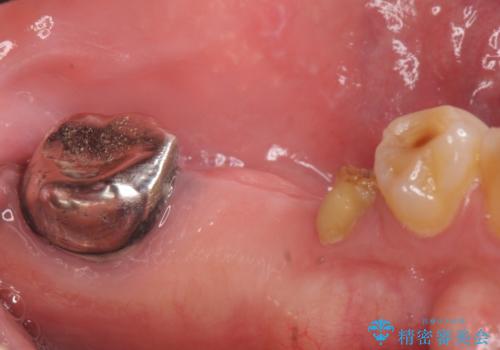

- 左下奥歯が虫歯で抜歯になってしまったため、インプラントにしたいといらっしゃった方の症例です。

欠損部位である左下5、6番目にインプラントを埋入し、オールセラミッククラウンによる補綴を行いました。